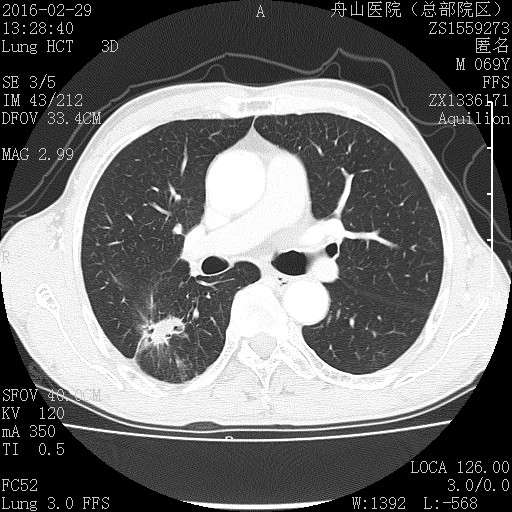

许多小白球--隐球菌,不做PAS及六铵银特染也看得清 荚膜的感觉明显 第三例的CT